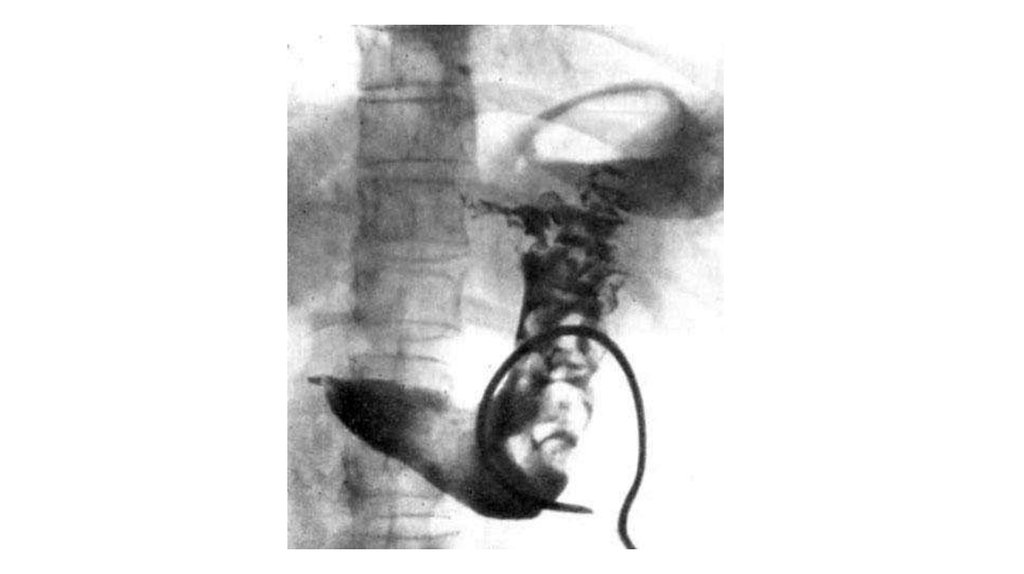

9. Рентгенологические признаки

резко утолщенные складки слизистой желудка

межскладочные промежутки при этом расширены и

отечны

стенки желудка эластичны, перистальтика в норме.

Различают распространенную и ограниченную формы

аномалии. При ограниченной форме болезни Менетрие

обнаруживают скопление толстых извилистых складок,

которые значительно выступают в просвет желудка и

представляют собой дефект наполнения неправильной

формы, состоящий из «подушкообразных» образований.

Локализация - большая кривизна напротив угла желудка.

При распространенной форме - в своде, теле и синусе

желудка. При этом в антральном отделе выявляют

нормальные складки.